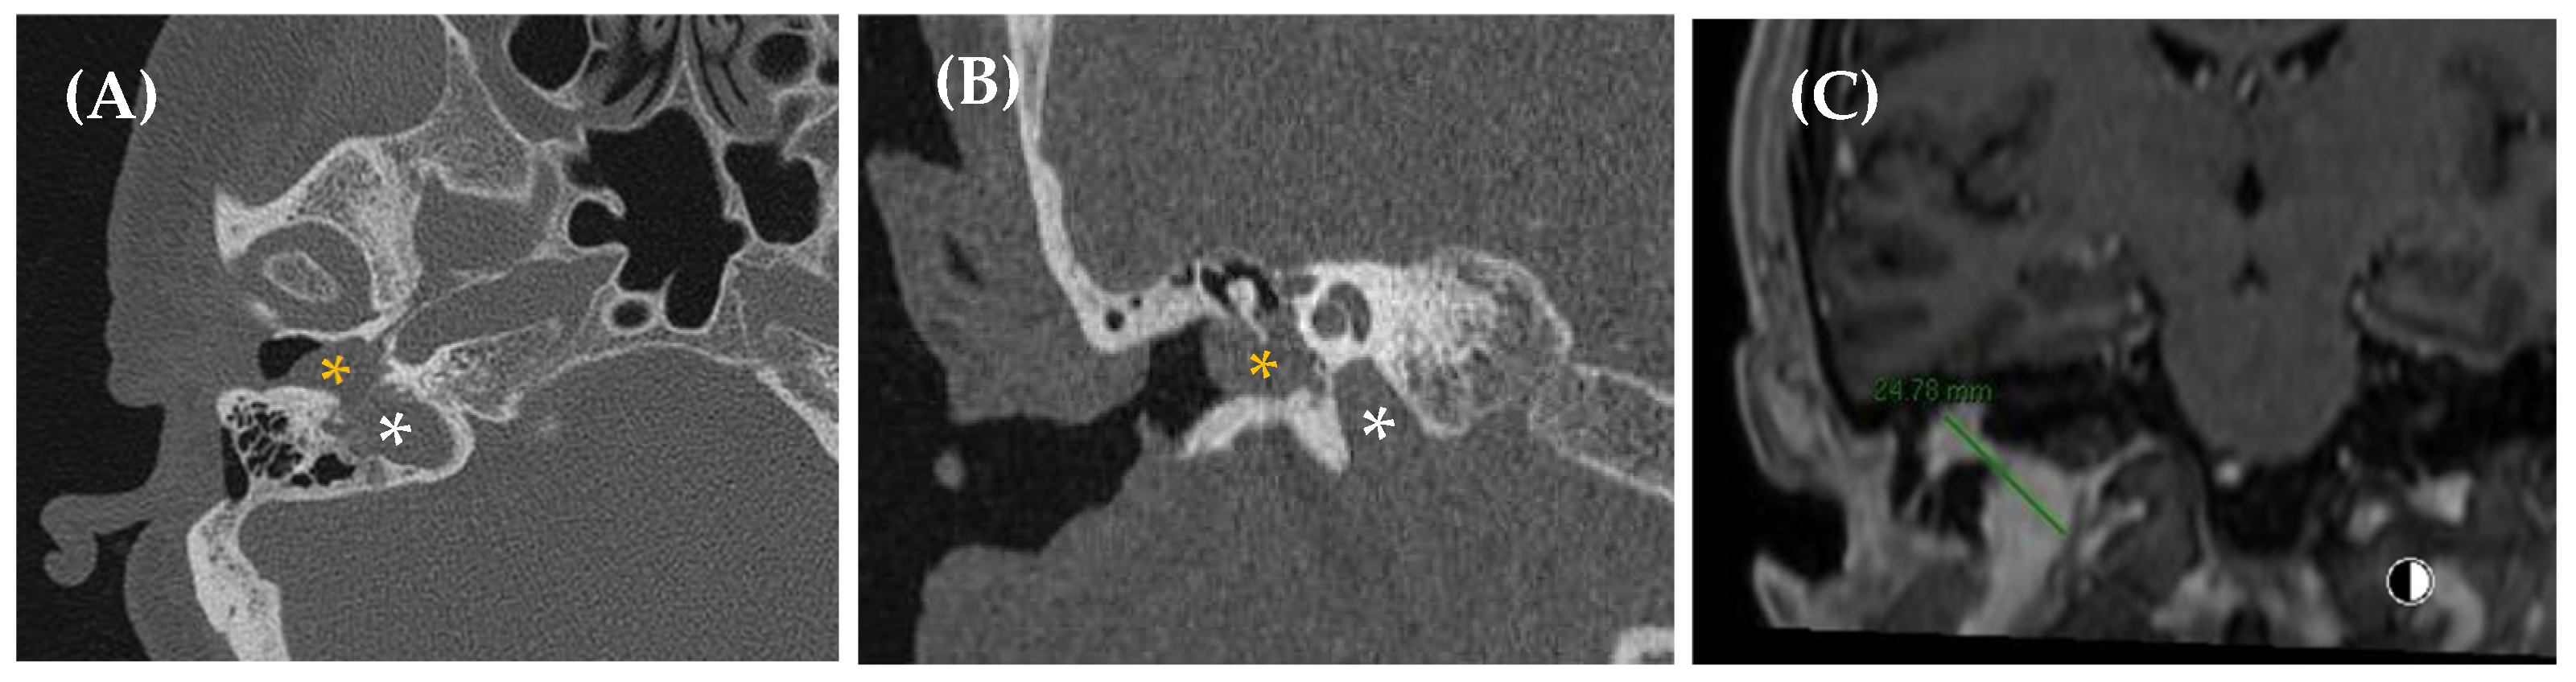

- Temporal bone abnormalities

- Superior canal dehiscence syndrome

- Kontorinis, G.; Lenarz, T. Superior semicircular canal dehiscence: A narrative review. J. Laryngol. Otol. 2022, 136, 284–292. [Google Scholar] [CrossRef]

- Ward, B.K.; Van de Berg, R.; Van Rompaey, V.; Bisdorff, A.; Hullar, T.E.; Welgampola, M.S.; Carey, J.P. Superior semicircular canal dehiscence syndrome: Diagnostic criteria consensus document of the committee for the classification of vestibular disorders of the Bárány Society. J. Vestib. Res. 2021, 31, 131–141. [Google Scholar] [CrossRef] [PubMed]

| Temporal bone abnormalities | Superior semicircular canal dehiscence Otosclerosis Paget’s disease Sigmoid sinus dehiscence/dehiscent jugular bulb Petrous carotid canal dehiscence |